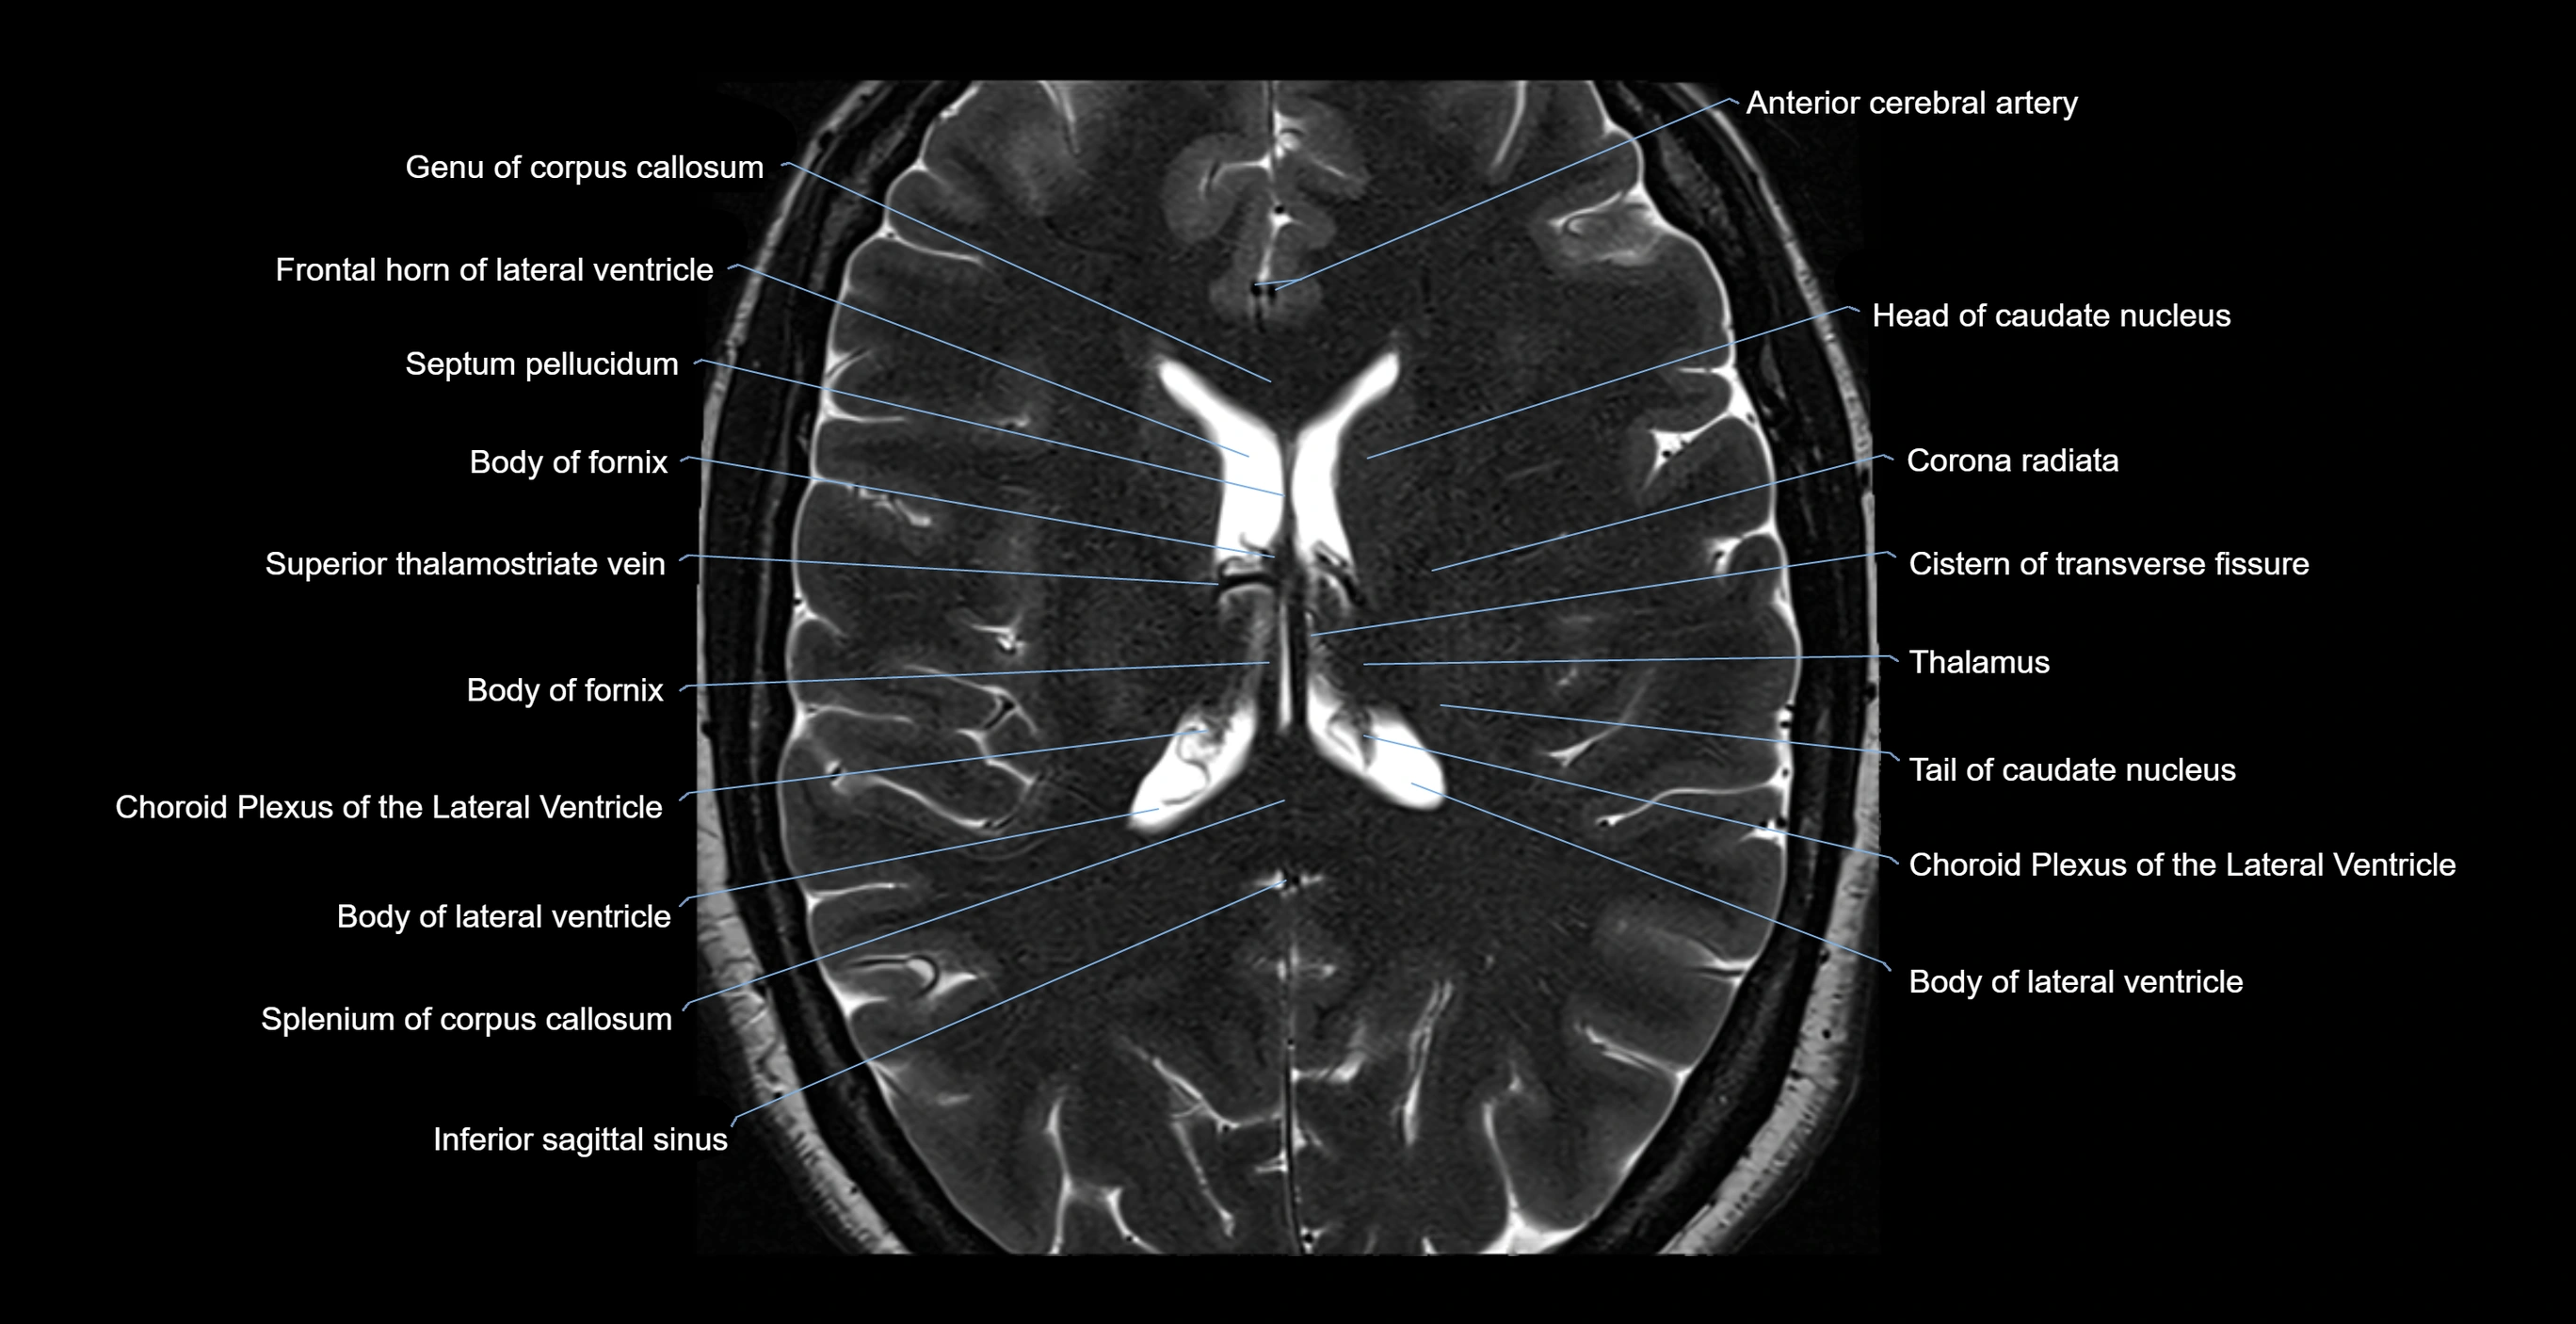

- Anterior cerebral artery

- Body of caudate nucleus

- Body of fornix

- Body of lateral ventricle

- Choroid plexus of the lateral ventricle

- Cistern of transverse fissure

- Corona radiata

- Crus of fornix

- Frontal horn of lateral ventricle

- Genu of corpus callosum

- Head of caudate nucleus

- Inferior sagittal sinus

- Occipital horn of lateral ventricle

- Septum pellucidum

- Splenium of corpus callosum

- Superior thalamostriate vein

- Tail of caudate nucleus

- Thalamus